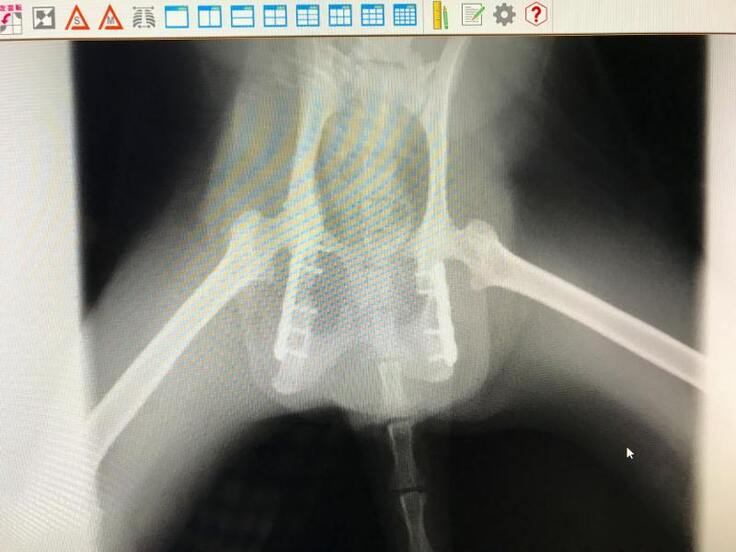

脚が立たないようなので仔猫2匹とクロちゃんを一緒に保護して動物病院で診察してもらうと、骨盤骨折していました。

初診のレントゲンでは骨盤の左側が骨折という診断で手術を受けましたが、手術後のレントゲンで右側も骨折していて、粉砕骨折しているという結果でした。

2回目の手術を受けて今はリハビリ中です。

交通事故に遭ったのだと思いますが、骨盤骨折して立てない動かない脚を前脚だけで引き摺って仔猫の元に帰ろうともがいて頑張って家の前まで帰って来ていたクロちゃん、なんとかうまく骨がつながって普通に歩いて走ってジャンプできるようになって欲しいと思います。

骨盤骨折しても必死で仔猫の元に帰えろうとしていたクロちゃんの骨盤骨折(粉砕骨折)を手術して元のように歩いて走ってできるようにしてやりたい。

長く待てないので、既に骨盤骨折の手術を2回受けました。

今は徐々に回復してヨタヨタしながらでも歩けるようになっていてリハビリ中です。